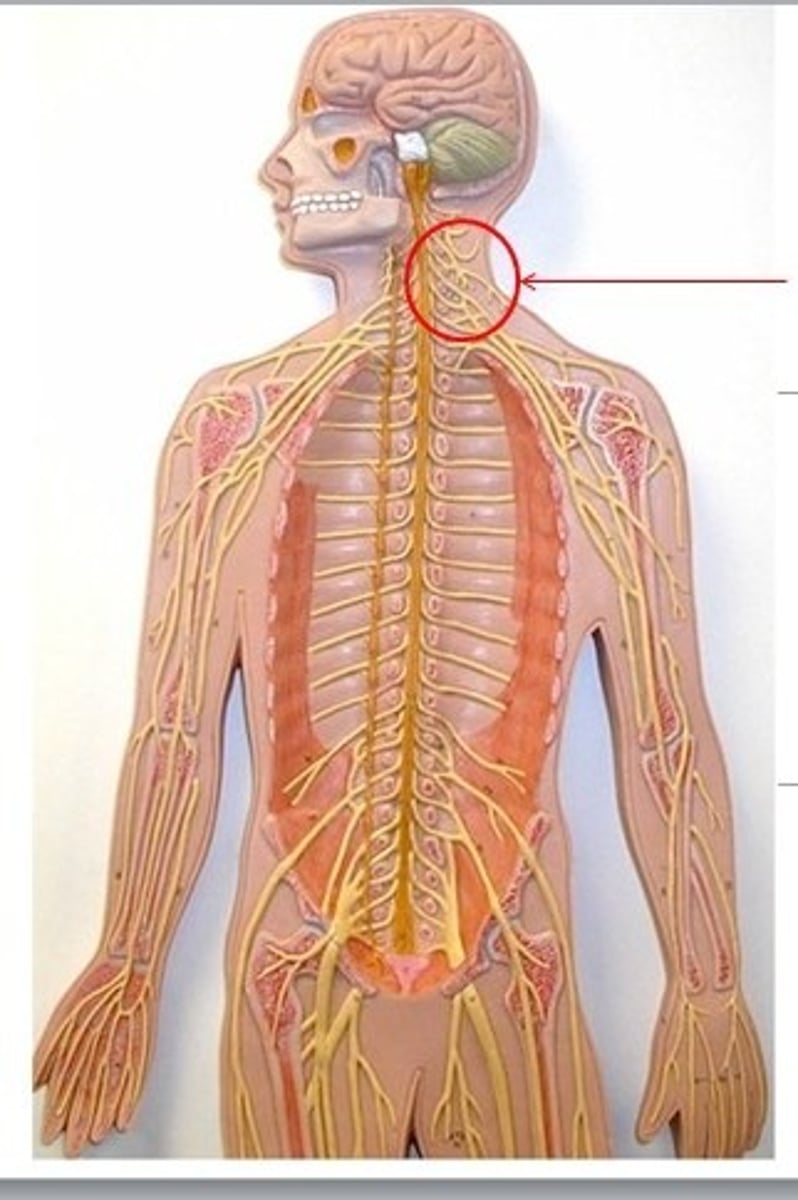

cervical plexus

C1-C5

brachial plexus

C5-T1

lumbar plexus

T12- L4

sacral plexus

L4- S4

phrenic nerve

neon purple (on neck)